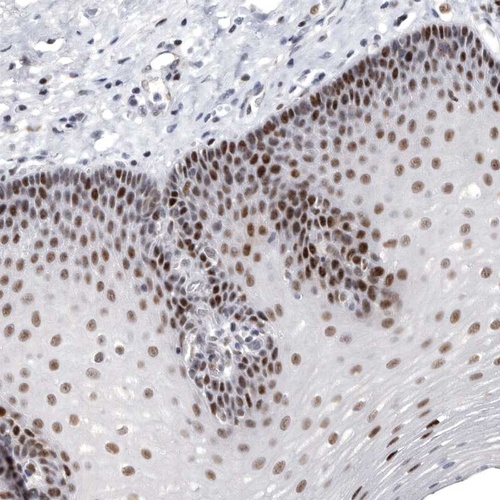

Immunohistochemical staining of human esophagus shows strong nuclear positivity in squamous epithelial cells.